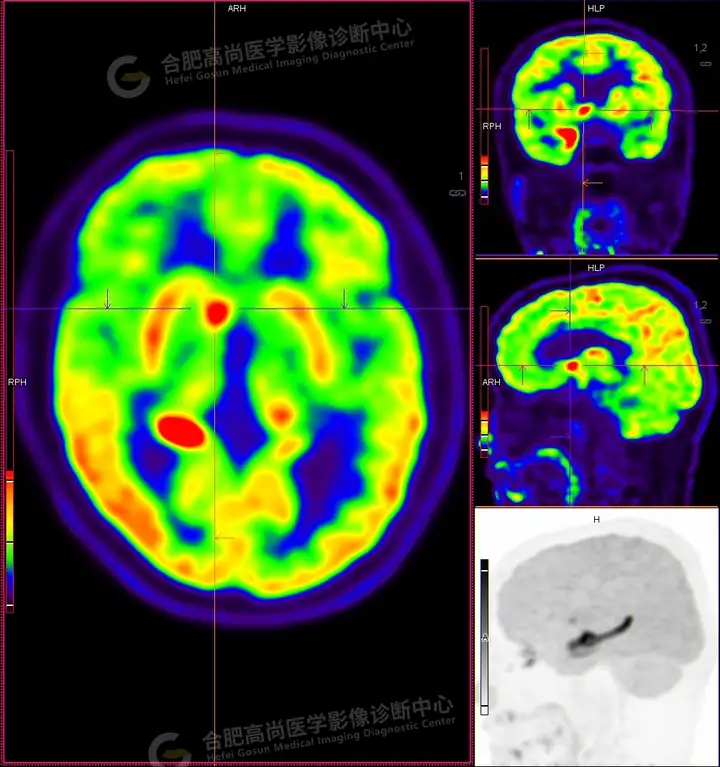

18F -FDG PET/CT检查图像:

18F -FDG PET/CT检查所见:

发作间期显像:PET显像双侧海马呈放射性摄取异常增高,以右侧明显,右侧海马SUVmax16.1、SUVavg4.4,左侧海马SUVmax7.3、SUVavg3.1(同层面额叶脑皮质SUVmax5.9、SUVavg2.3);CT示左侧海马体积较右侧似轻度缩小,左侧侧脑室颞角轻度增宽。PET显像右侧杏仁核及右侧基底节区局灶性放射性摄取异常增高,SUVmax14.1、SUVavg5.7(左侧SUVmax5.1、SUVavg3.6);CT示右侧杏仁核及右侧基底节区大小、形态正常,未见异常密度灶。

18F -FDG PET/CT检查结论:

发作间期显像:双侧海马、及右侧基底节区FDG代谢异常增高,考虑致癫灶可能大,请结合临床。